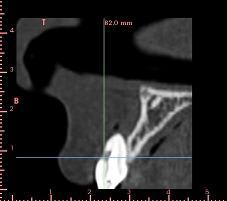

pour la 21, çà va...mais la 11 est à bout de souffle...avec l'apex qui traverse la gencive vestibulaire...

veut un implant...forcément...mais là, faut une greffe...plutôt importante...

bon, autre truc plutôt défavorable au greffon ramique...je viens de vérifier: contact des apex de 38 et 48 avec le NDI...et comme les dds ont suffisamment de place...on laisse tranquillement évoluer...

Sinon concernant ton cas j'ai l'impression qu'il y a de l'os en mesial et distal de ta dent du coup si c'est bien le cas je ferais de la rog avec une membrane pinsee